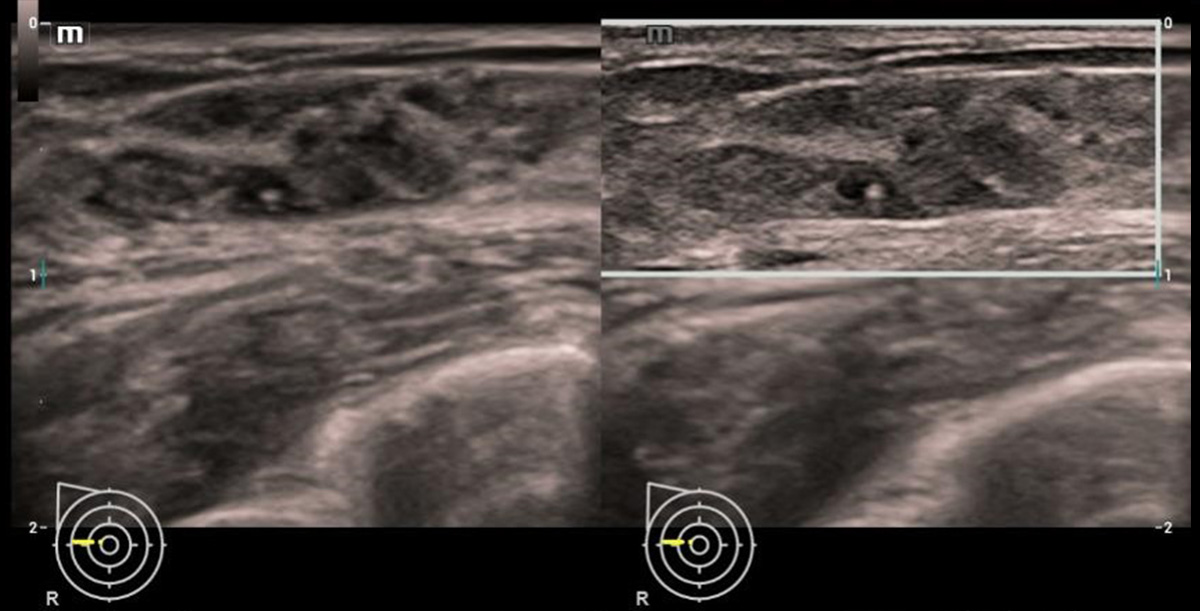

HD Scope

Migliora le informazioni di dettaglio e il contrasto dell'immagine su un'area specifica, particolarmente utile per la visualizzazione dei margini e della struttura interna

HD Scope

Smart Breast

Smart Breast Ăš uno strumento di analisi e refertazione delle ecografie mammarie che rende la routine clinica delle ecografie mammarie piĂč accurata e produttiva. La gestione sistematica delle lesioni multiple e la valutazione a quattro piani garantiscono ulteriori informazioni diagnostiche. Inoltre, il flusso di lavoro automatizzato semplificato fornisce una scansione del seno piĂč efficace.